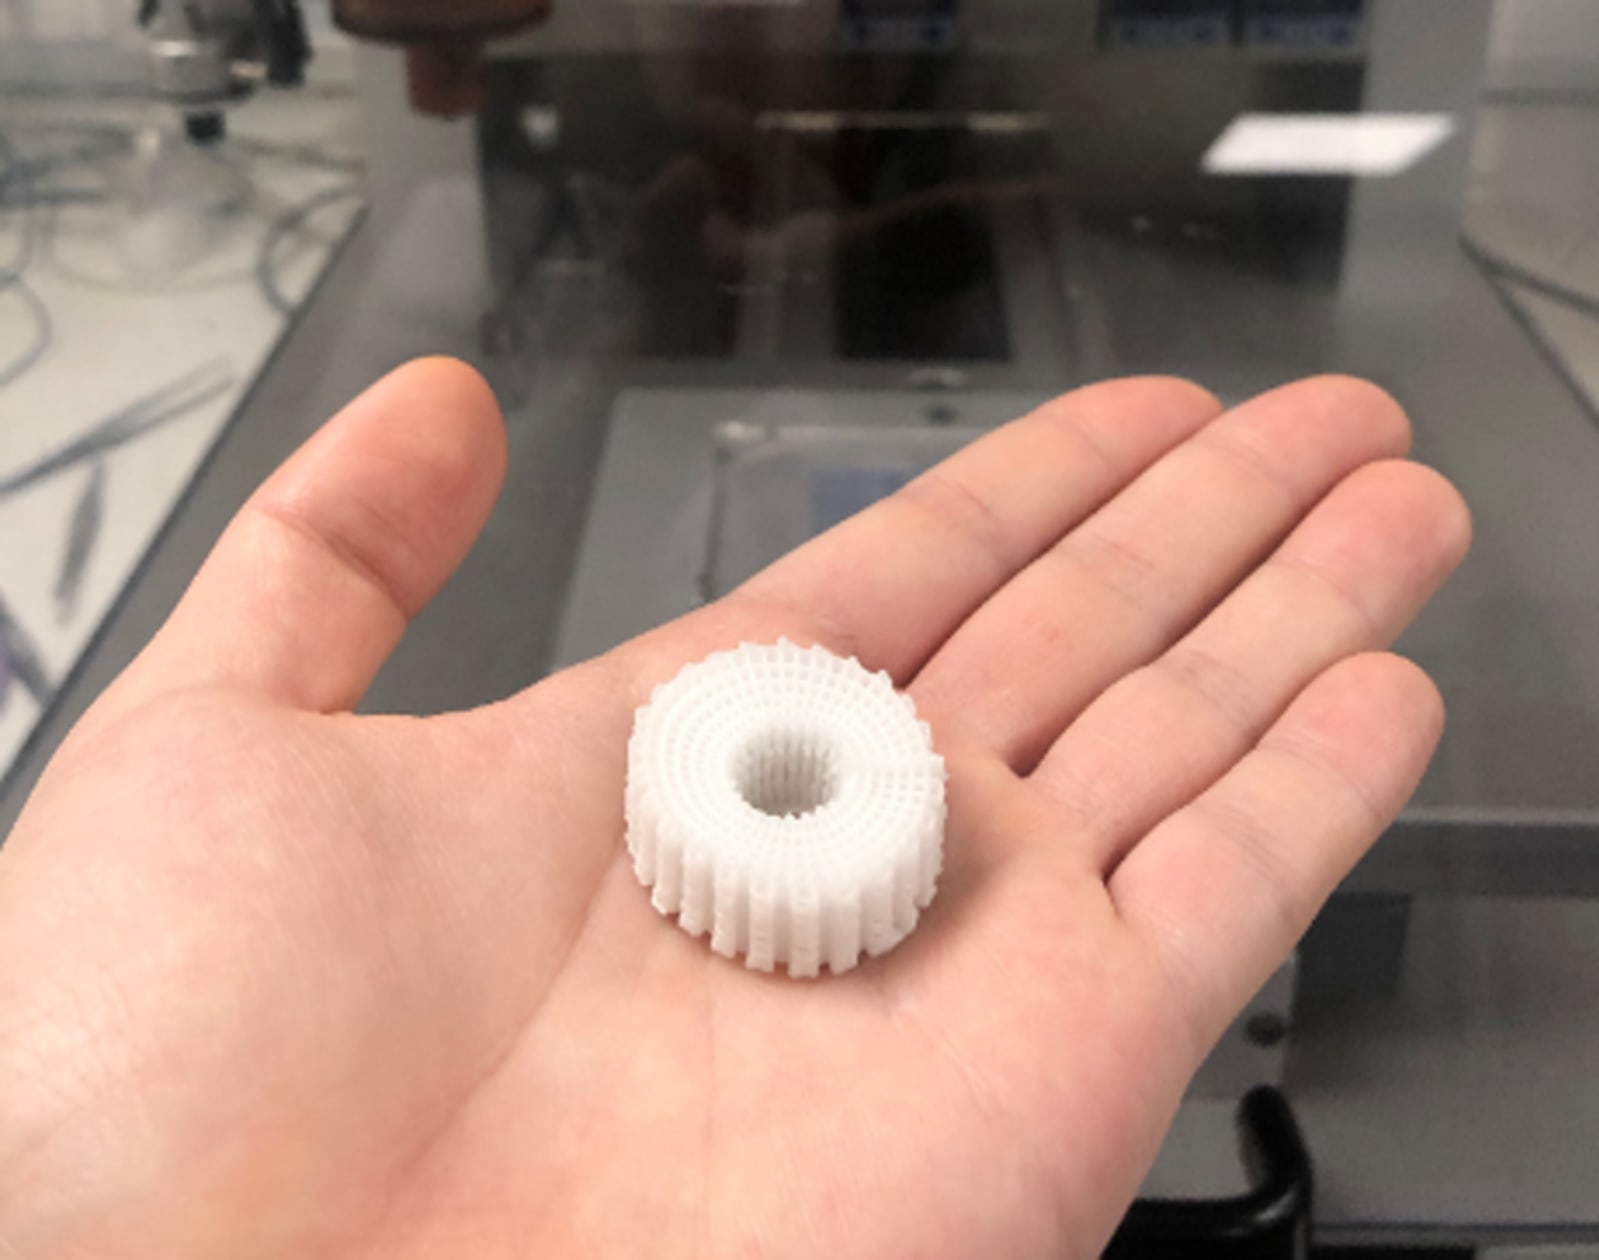

These bone bricks are designed to click together like Lego bricks, creating a personalized fit for blast victims at a time of critical need at Syrian refugee camps.

This is where the newly conceived 3D-printed bone bricks come in. The treatment uses medical scaffolds made of polymer and ceramic materials, which can be clicked together to create a temporary structure that perfectly fills the bone gap caused by the blast injury. These bone bricks would have all the support of a normal bone in compression, while inducing the formation of new bone tissue around the structure. As the bone regenerates, the bricks dissolve. Each of these degradable bricks has pores containing antibiotic ceramic paste, which combats infection in a remarkably practical way during the healing period.

This limb-salvaging solution uses low-cost 3D-printing technology and can be executed in a relatively straightforward manner. All a clinician has to do is piece together a collection of ready-made bricks to create a custom-fit structure for a particular defect. The treatment is expected to cost less than USD$245 (GBP£200) for a typical 100mm fracture injury, as opposed to other methods which can cost anywhere from $330 to $1,230 (£270 to £1,000).